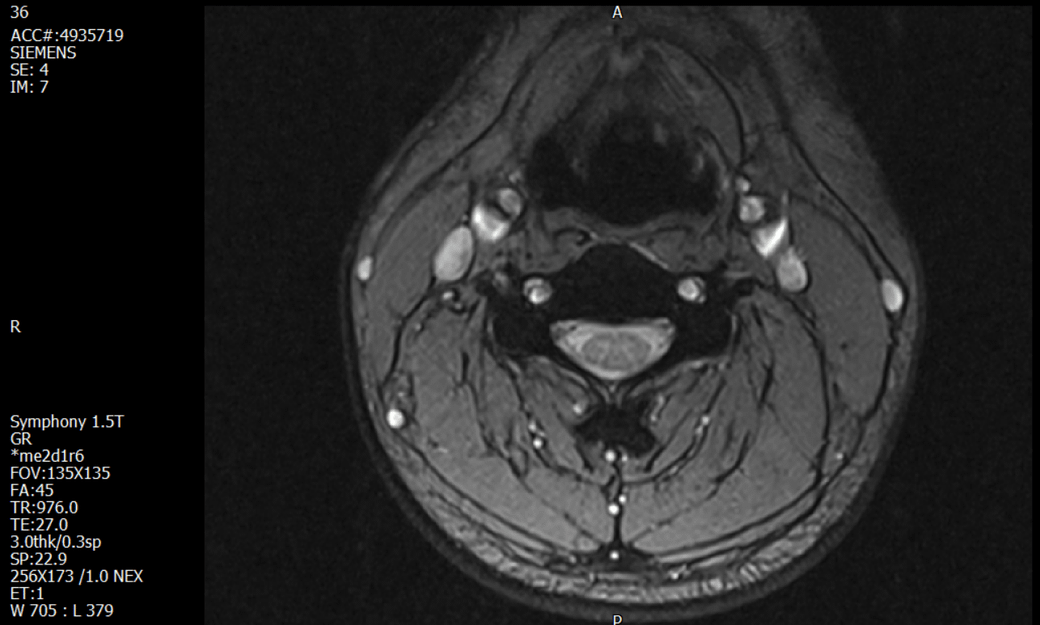

경추 요추 디스크 MRI판독 부탁드립니다.

-11월, 증상발생 직후 잠실소재 척추전문병원 MRI 요추경추 촬영 후 신경외과 박사 진료, 허리는 매우 건강, 경추는 퇴행성 진행되고 있지만 디스크라고 보기 어려움. 신경막만 살짝 건드리는 정도고 이 정도로 힘빠짐이나 저림이 오지 않고 원인은 다른 곳에 있을 가능성.

1. MRI 상 , 경추와 요추에 디스크가 있나요? 있다면 좌측 팔과 다리에 저림 및 힘빠짐을 줄 정도인가요?

• 4번 째 사진

• 1. MRI 사진을 보았을 때 디스크를 의심해볼 수 있는 소견이 살짝살짝 보이긴 합니다만, 상하지의 저림 및 힘빠짐을 유발할 정도인지는 솔직히 회의적입니다.

3. 개인적으로는 디스크로 인한 증상이 아닐 것으로 보나, 만약 디스크가 맞다면 우연하게 목과 허리 디스크 발병이 이틀 간격을 두고 나타났을 가능성을 생각해야 하는데, 현실적으로 그 가능성이 높지 않습니다.

4. 말씀하신 것처럼 특히 요추부 MRI는 디스크를 찾기 어렵습니다.